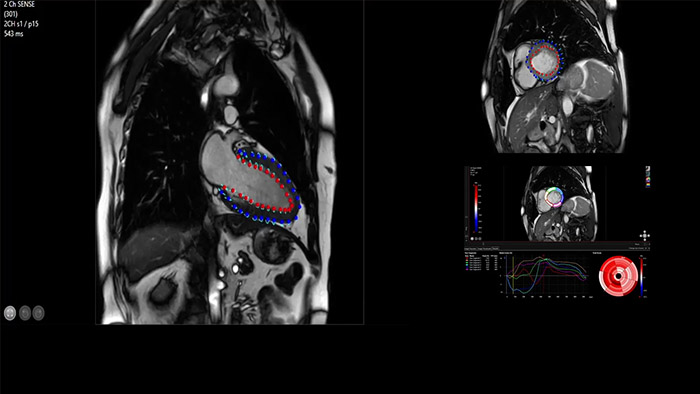

Accelerate workflow for your cardiac exams

IntelliSpace Portal offers a Comprehensive Cardiac MRI Suite, providing dedicated workflows for functional analysis, viability, LGE, cardiac mapping assessment and RV/LV functional analysis in less than 5 min. per case1.

Quantify Myocardial Strain

IntelliSpace Portal MR Caas5,6 Strain7 assists in patient diagnosis and monitoring by providing global strain parameters such as global longitudinal strain (GLS), global circumferential strain (GCS), and global radial strain (GRS), using short and long axis MR images, as well as describing the myocardium deformation- such as shortening, thickening, and lengthening during the cardiac cycle.